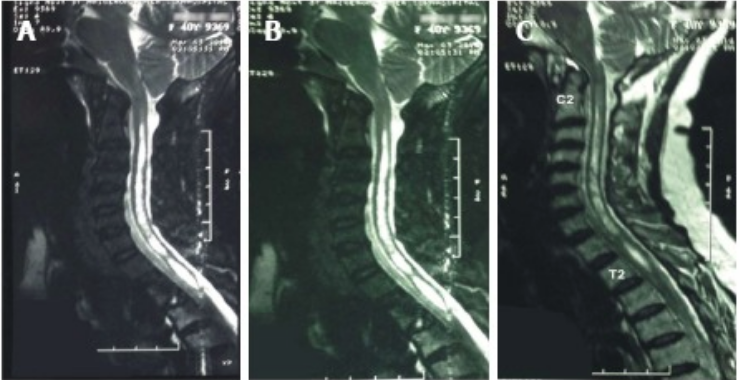

Neuropathic arthropathy of the shoulder is a rare disorder characterized by joint degeneration, and is associated with loss of sensory innervation. Syringomyelia is a disease in which fluid-containing cavities (syrinxes) form within the spinal cord. Here, we report a case of neuropathic arthropathy of the shoulder secondary to syringomyelia in a 40-year-old woman. X-rays of the left shoulder revealed damage to bone and joint architecture. Blood tests indicated vitamin D deficiency and secondary hyperparathyroidism. Magnetic resonance imaging of the cervical spine showed a large syrinx from the second cervical spine to the second dorsal spine. Although neuropathic arthropathy is uncommon, it should be considered in cases of unexplained pain, discomfort, or limited range of motion of the affected joint. Symptoms related to the affected joint may precede or overshadow neurological deficits. Appropriate radiological examinations and diagnoses are imperative to prevent misdiagnosis or undetected bone and joint disorders.

Keywords: Neuropathic arthropathy, Charcot shoulder, Syringomyelia, Magnetic resonance imaging, Vitamin D deficiency